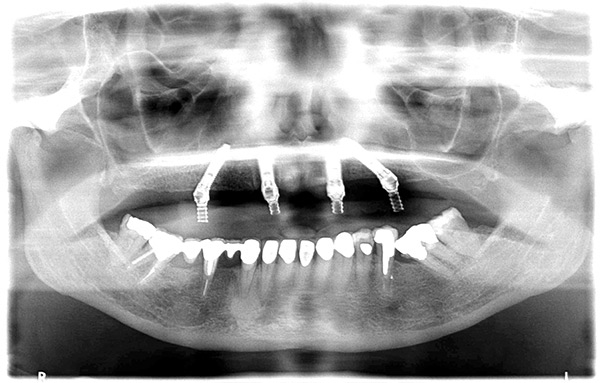

Fig 1. A radiograph of the All-on-4 concept depicting two axially orientated implants in the anterior and two tilted implants in the posterior.

Figure 1